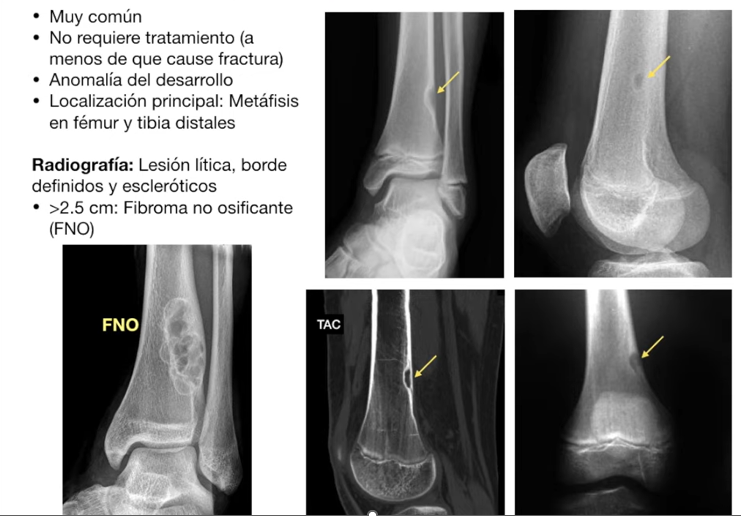

defecto fibroso cortical / fibroma no osificante